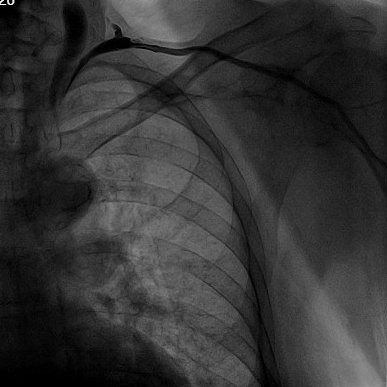

术中于左侧腋下、锁骨下进行多次穿刺,均失败,后行肘静脉造影。

造影自肘静脉至腋静脉段逐渐变窄变细,直至消失,判定左侧无传统起搏器入路路径,改右侧植入,多次穿刺,再次失败,行静脉造影。